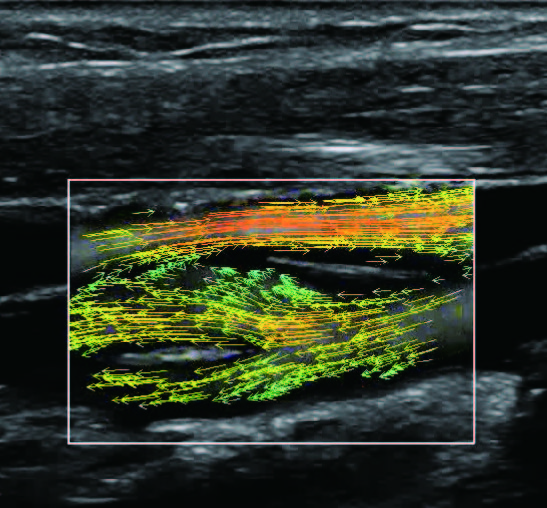

На изображениях, приведенных ниже показаны примеры из клинической практики врачей ультразвуковой диагностики, полученные в процессе апробирования прибора Mindray Resona 7. Приводится наглядные примеры сравнения традиционного режима ЦДК и режима V Flow (Vector Flow).

vflow_5_1.jpg   vflow_5_2.jpg

vflow_6_1.jpg   vflow_6_2.jpg

Изображена яремная вена и бифуркация сонной артерии. CAA, ICA и ECA показаны на одном изображении. В режиме ЦДК отсутствует подробная гемодинамика. В режиме V Flow отображаются данные о скорости и направлении движения частиц крови во всей зоны интереса, включая изменения характеристик кровотока в сонной артерии и яремной вене.